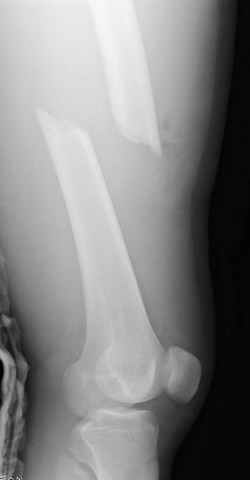

03.14.2005

больному 42, автоавария, политравма, открытая черепномозговая травма, безсознании, открытый перелом бедра, размозжение мягких тканей, дефект кожи на передней поверхности бедра около 13 см2 от ожога, компартмент синдром.

По поводу открытого перелома больной ургентно взят на ретроградное интрамедулярное штифтование, после рутинного дебрайдмента и фасциотомии на бедре и на голени.

перелом бедра